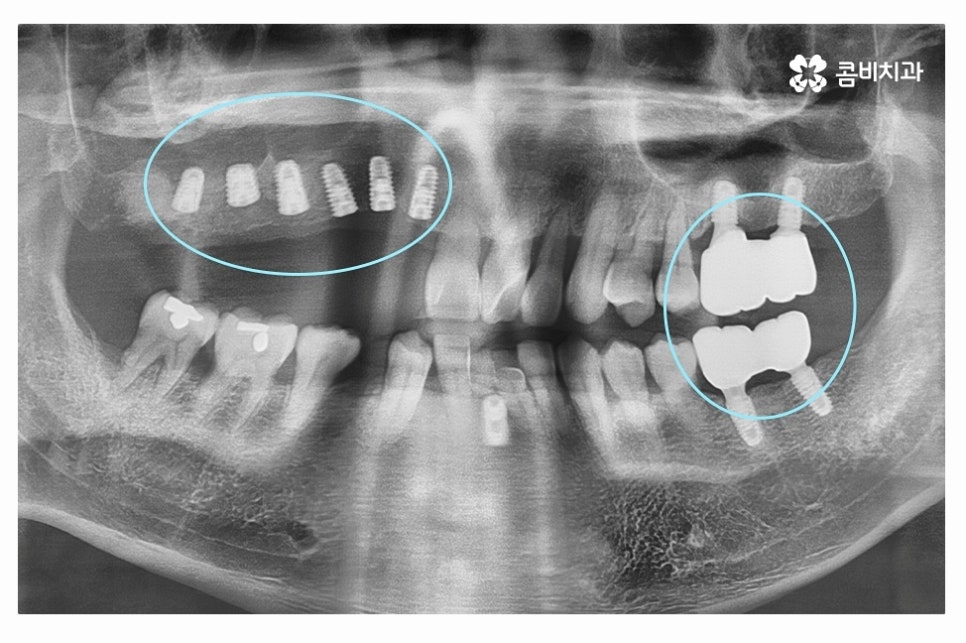

중년 이후에는 치아 상실의 원인이 치주질환으로 인한 경우가

많기 때문에 위 엑스레이 사진에서 보시는 것처럼

치아 자체는 멀쩡해 보이지만 잇몸 상태가 악화되어서

치아를 발치하고 임플란트 수술을 하는 경우가 많다고 볼 수 있어요.

충치로 인해 치아를 잃게 되는 경우에는 치아 하나를

대상으로 임플란트를 하게 되지만 치주질환으로 인해

여러 치아를 한꺼번에 잃게 되는 경우에는 치료비 부담이 클 수 있는데요.